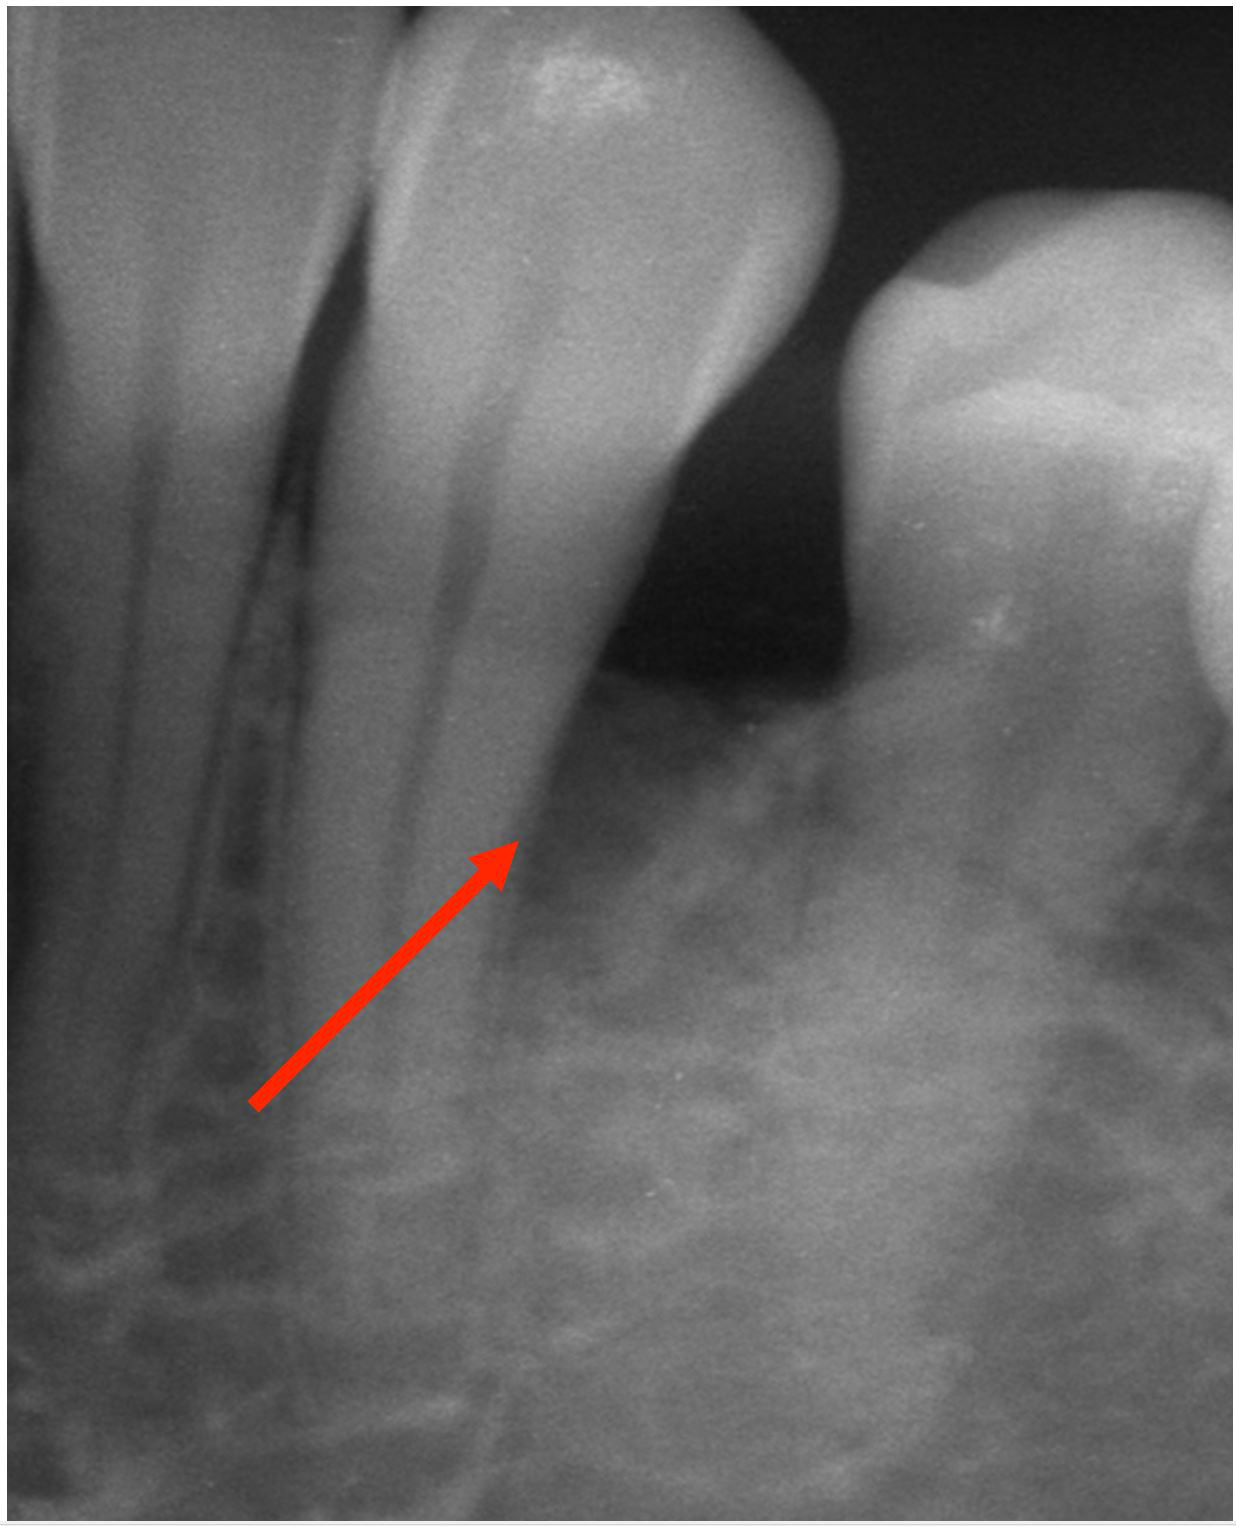

Laser for Periimplantitis

Laser Periodontal Treatment

*Follow-up x-rays 9-12 months after treatment